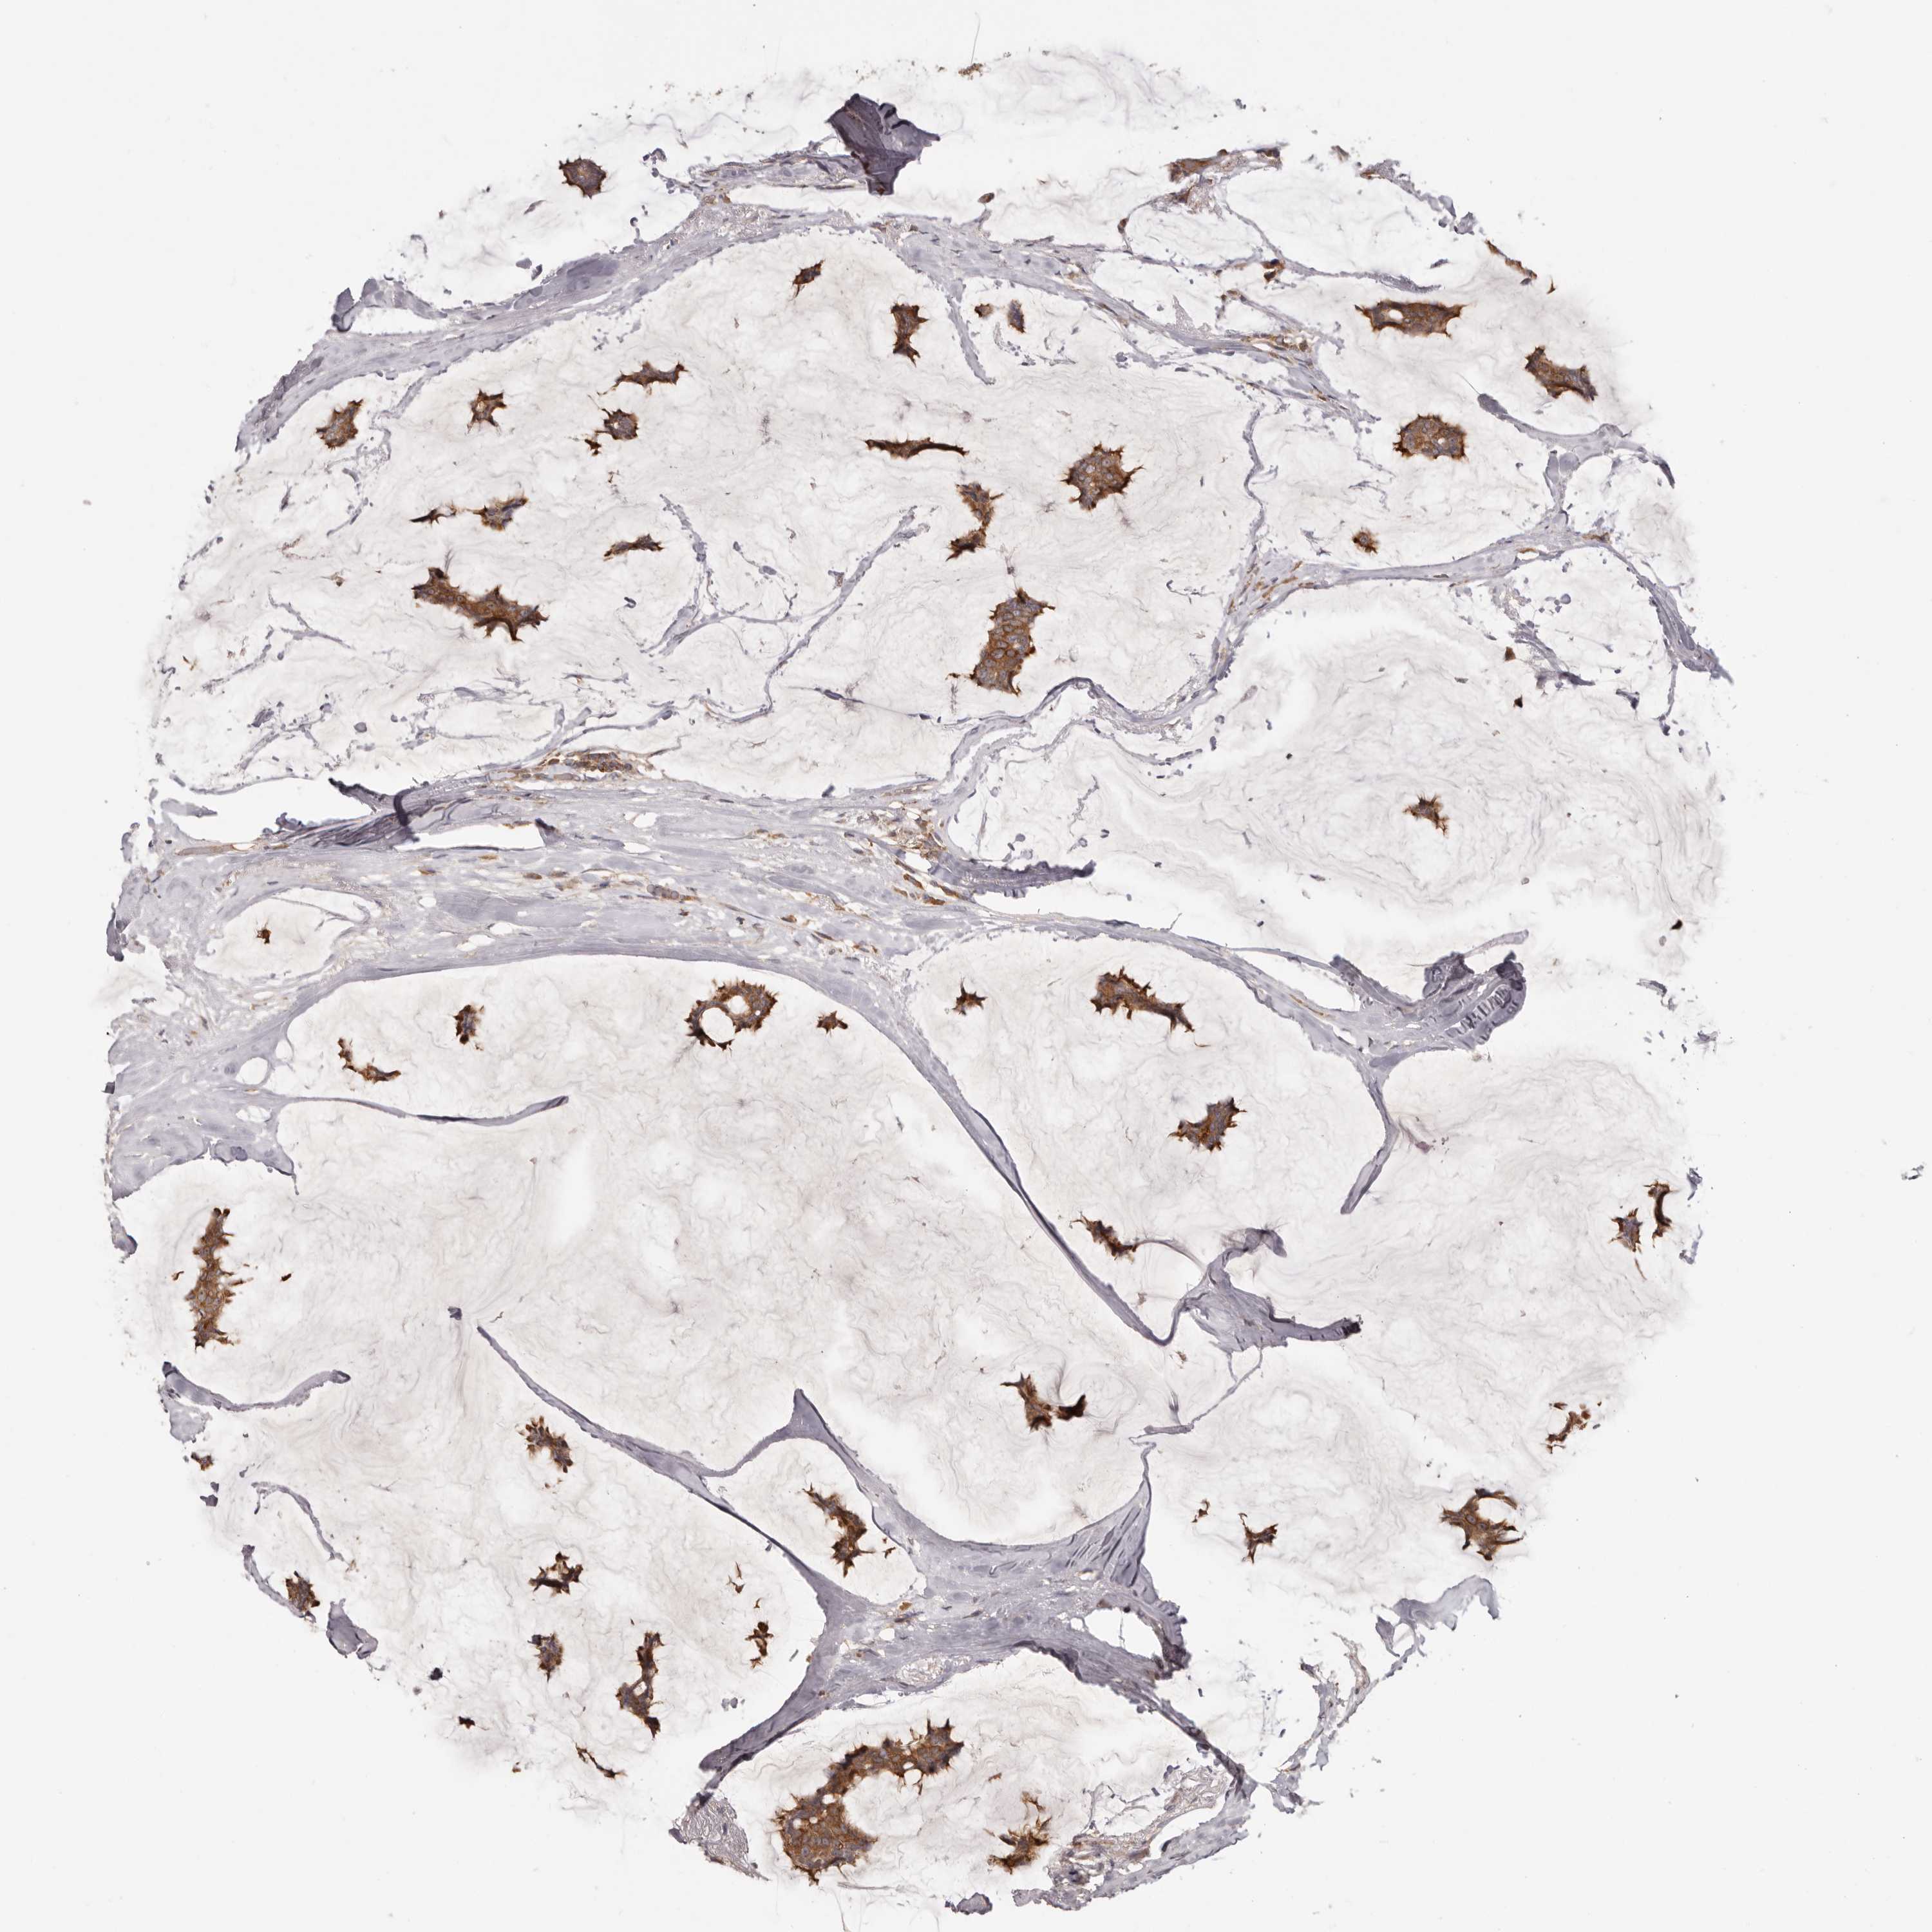

CANCER BREAST CANCER Show tissue menu

BRCA TCGA BRCA VALIDATION PROTEIN EXPRESSION

Breast cancer

Human cancer

EEF1E1 is potential prognostic, high expression is unfavorable in Breast Invasive Carcinoma (TCGA)